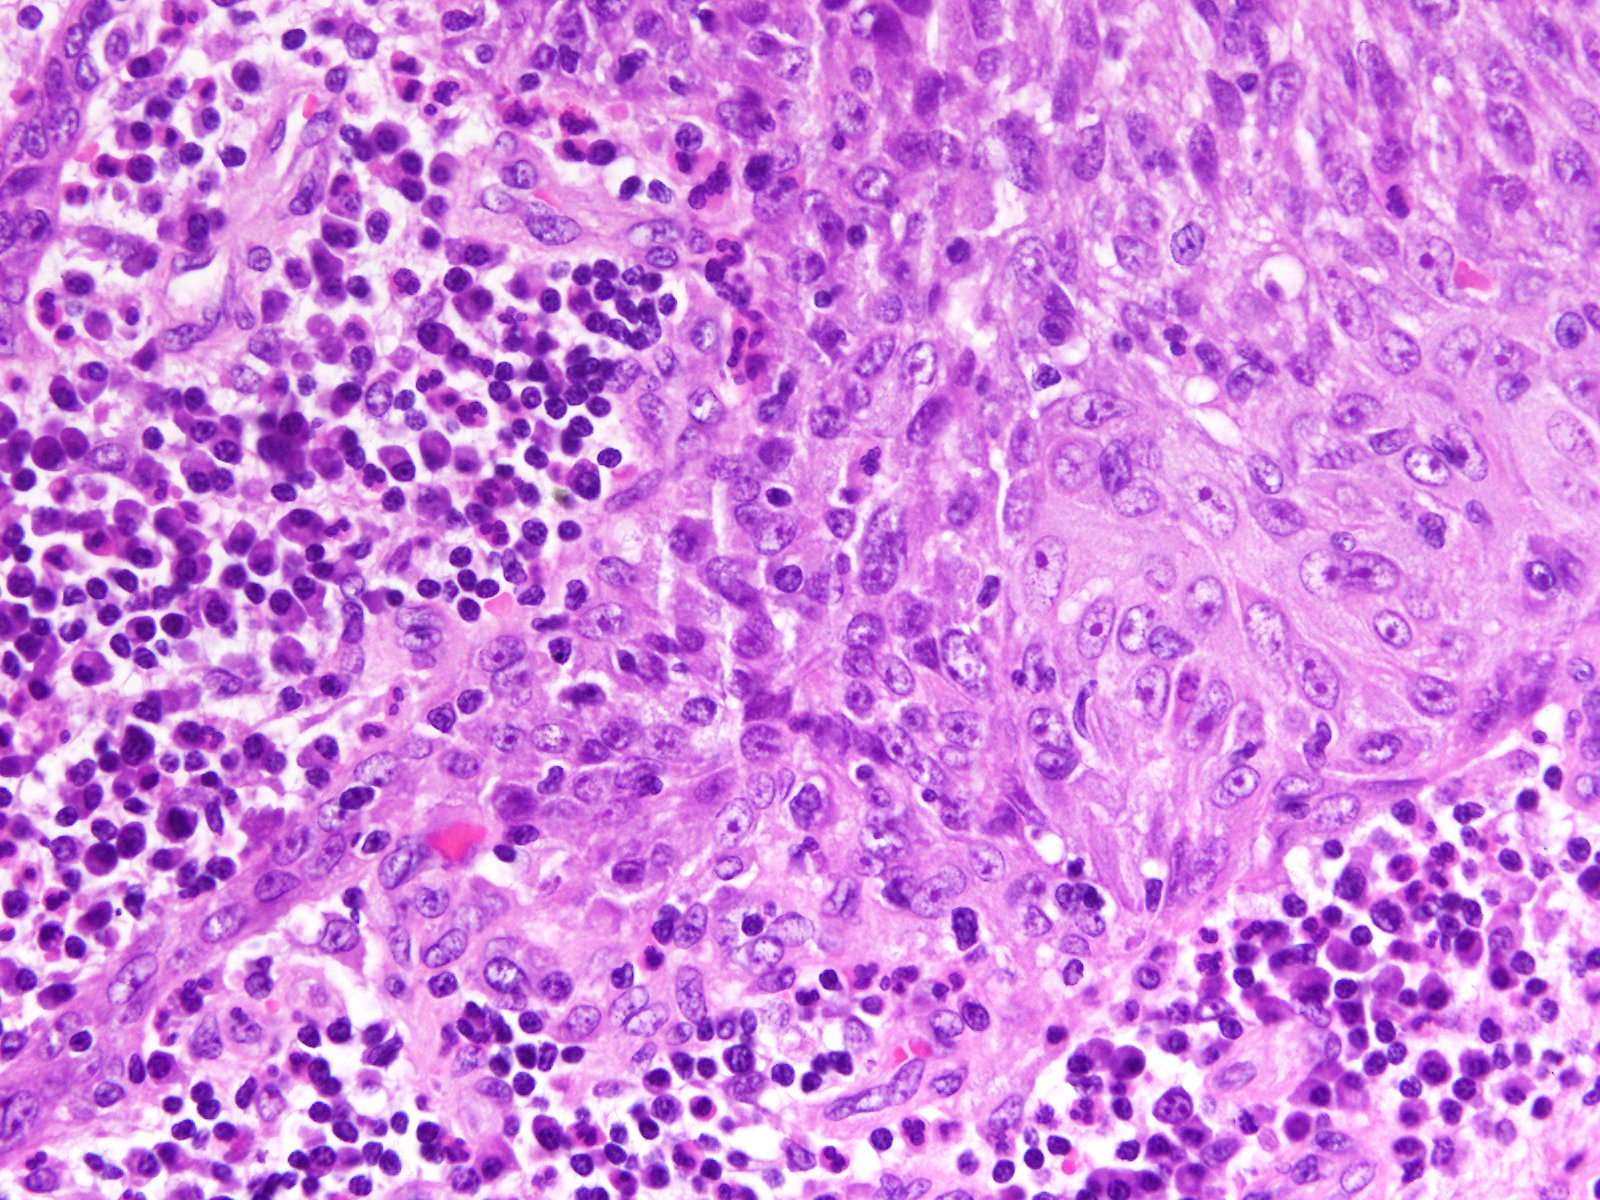

Consensus grade: High-grade papillary urothelial carcinoma (HG-PUC)

Case description (by case creator):

Papillary tumor in TUR-BT.